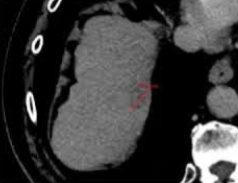

局部肿瘤进展 Local tumor progression (per-nodule)

中位随访时间:25.6 个月

局部肿瘤进展(LTP) 81/304 例(占 26.6%)

局部肿瘤进展 LTP 中位时间:14.8 个月

IRE 完全消融后的(LTP)累积发生率:

1 年期:19.4%

2 年期:32%

3 年:36.1%

3年LTP总体发生率(包括首次 IRE 失败的情况):

直径≤ 2 厘米27.5% 适用于的肿瘤 为

直径2 - 3 厘米48.4%(对数秩检验 p < 0.01) 55.9% 适用于肿瘤

直径大>3 厘米55.9%(对数秩检验 p < 0.01)